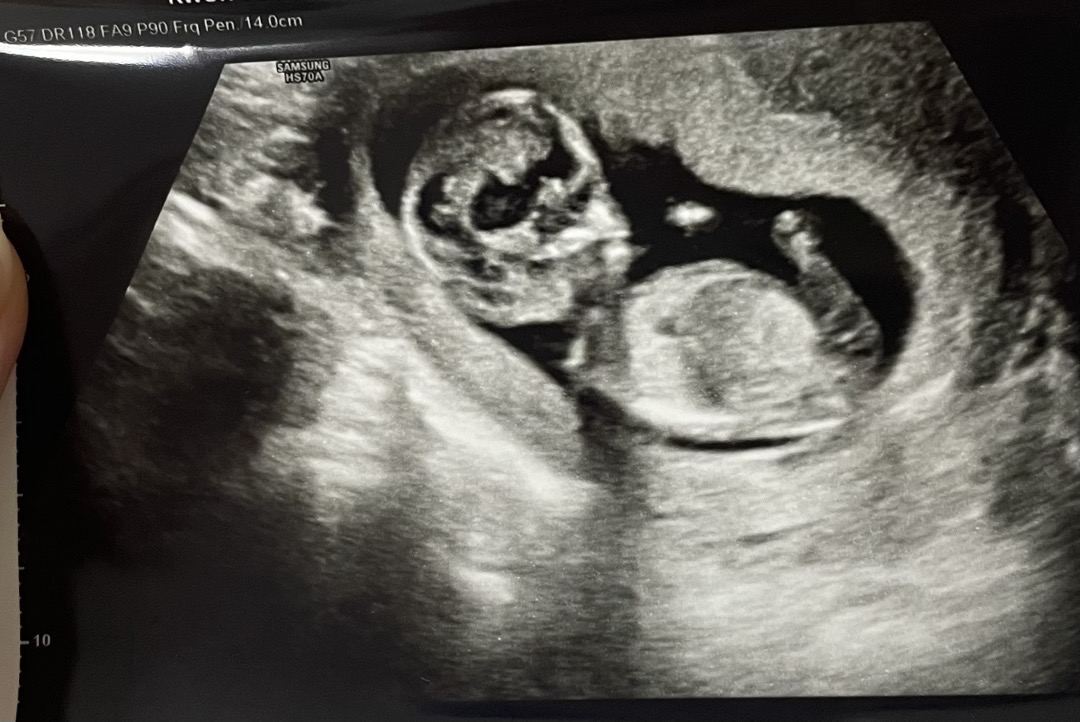

아들딸궁금 각도법고수님들!

궁그매욧🥹🥹🥹